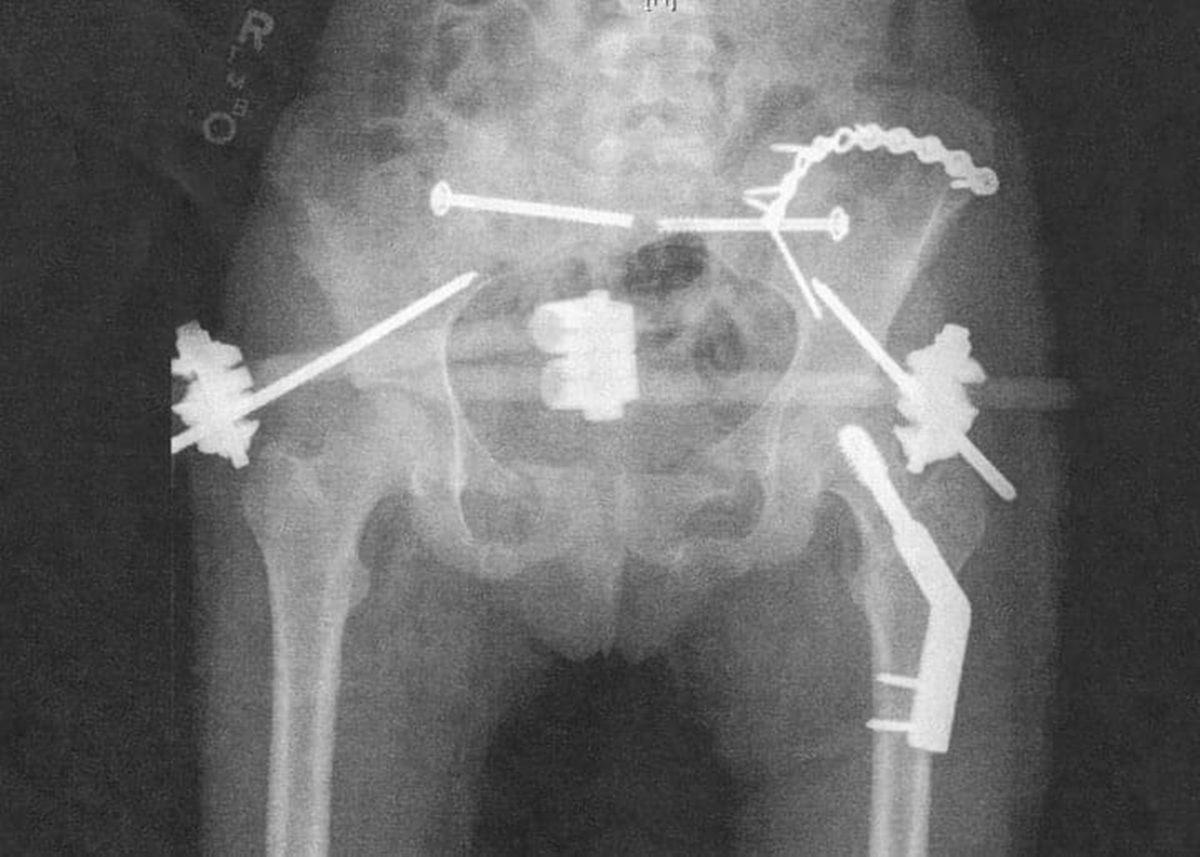

- Kaza sonrasında arabadan fırlayan bir adamın pelvis röntgeni.

Yedi yerinden kırılan pelvisinin, yerine oturtulabilmesi için çok sayıda vida ve harici bir sabitleme cihazı gerekmiş.

Emniyet kemerinizi takın!